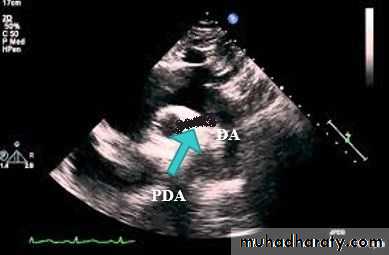

Functional closure of the ductus normally occurs soon after birth, but if the ductus remains patent when pulmonary vascular resistance falls, aortic blood is shunted into the pulmonary artery.

The aortic end of the ductus is just distal to the origin of the left subclavian artery, and the ductus enters the pulmonary artery at its bifurcation.

The chest X-ray and ECG are usually normal with small PDA, but if the PDA is large and symptomatic the features on chest X-ray and ECG are indistinguishable from those seen in a patient with a large VSD.Echocardiography show the PDA and the cardiac chambers.